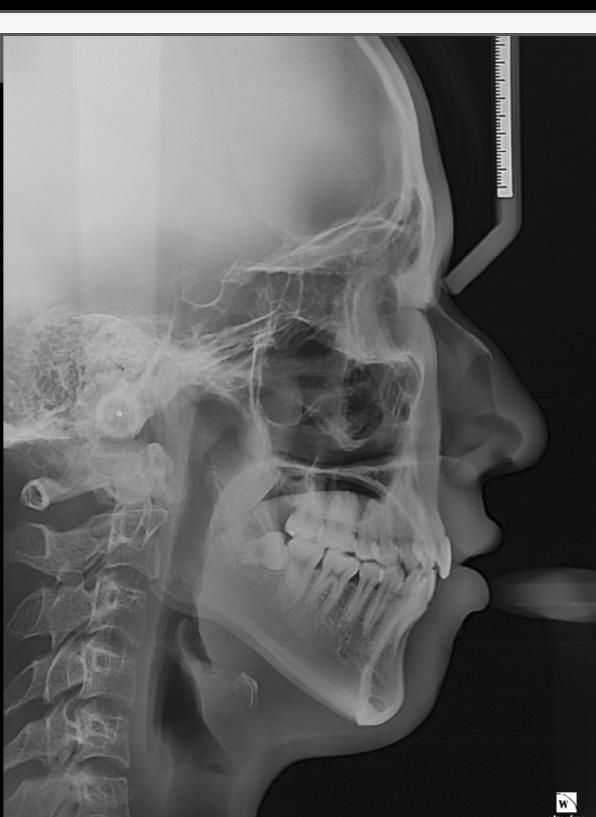

marpe을 1년동안 게속돌려서 다른사람들보다 marpe장치를 훨씬많이돌렸는데 귀에서 눈까지거리(얼굴앞뒤뼈가) 교정전보다 훨씬 커진것같은데 엑스레이상에서도 훨씬 커지게 나왔는데 확인부탁드립니다 귀에서 눈까지거리

제미나이한테물어보니 marpe을 저처럼 심하게 많이돌리면 위턱뼈가 확장될때 얼굴앞뒤뼈에도 간접적으로 영향가 커질수있다고...성인20대초남자입니다

• 1번 째 사진

간접적인 영향이지 직접적으로 영향을 미치지 않습니다. 또한 소아 청소년기에 이러한 변화가 나타날 가능성이 있으며 성인기에는 변화 가능성이 적다고 보시면 됩니다. 또한 다음 사진은 정확히 같은 지점을 계측하지 않았으므로 해당 사진만으로 판단할 수 없습니다.